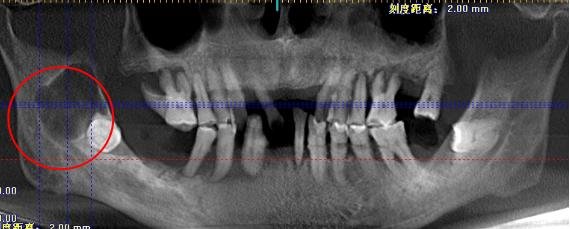

口腔科吴艳妮医师诊查中发现李爷爷右侧上下眼睑、眶下及右下面部肿胀明显,伴有压痛、张口中度受限、口内右下6、7缺损、未见右下8。右侧颊侧粘膜肿胀明显。CBCT示:右下8埋伏阻生,右下8根尖上方可见2.0*2.0cm的圆形低密度影。诊断为颌骨囊肿,需手术治疗。

考虑到李爷爷已年逾80,且在急性感染期,为其控制感染后,进行了右下8埋伏牙拔除术、颌骨囊肿摘除术,术后病检示“颌骨根尖囊肿”。

术前